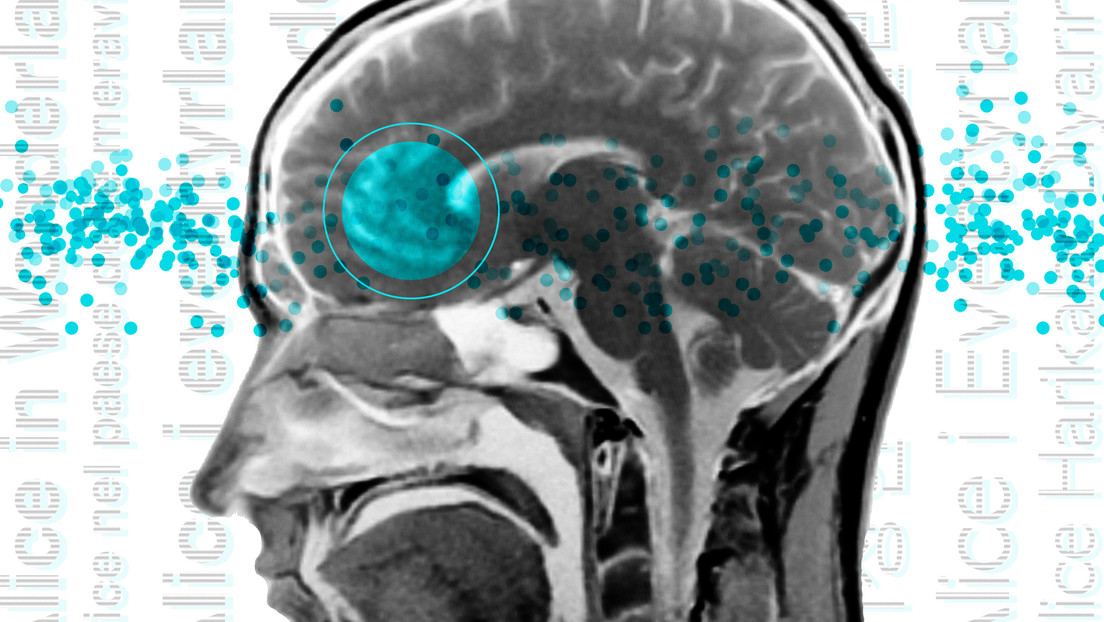

La mitad del cerebro humano está formada por materia gris, células nerviosas que procesan sensaciones, controlan el movimiento voluntario y permiten el habla, el aprendizaje y la cognición. La otra mitad es la llamada sustancia blanca, configurada principalmente por axones de neuronas, es decir, la parte de las neuronas encargada de conectar las zonas de materia gris entre sí y transmitir la información procesada al resto del cuerpo.

Al mapear la actividad cerebral en tres dimensiones, el equipo pudo separar y detectar de manera confiable señales de la materia blanca, abriendo la puerta a una mejor comprensión de esta otra mitad del cerebro, tradicionalmente menos estudiada, informa MedicalXpress.

Al estudiar escáneres cerebrales de personas diferentes grupos de edad, los investigadores encontraron que la conectividad general de diferentes regiones del cerebro disminuye gradualmente con la edad, pero al mismo tiempo aumenta la actividad en la corteza frontal, que desempeña un papel importante en la función cognitiva superior, es decir, en nuestra habilidad para enfrentar situaciones complicadas, como la toma de decisiones, la planificación y la creatividad.

Este cambio posiblemente compense la disminución en otras áreas, estiman los científicos.